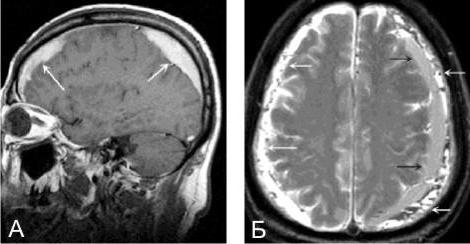

МРТ головного мозга. Массивная двухсторонняя хроническая субдуральная гематома.

При проведении МРТ может наблюдаться пониженная контрастность зоны острой гематомы; хронические субдуральные гематомы, как правило, отличаются гиперинтенсивностью в Т2 режиме. В затруднительных случаях помогает МРТ с контрастированием. Интенсивное накопление контраста капсулой гематомы позволяет дифференцировать ее от арахноидальной кисты или субдуральной гигромы.